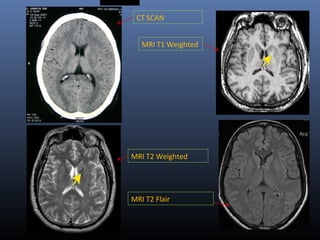

CT SCAN CSF Edema White

Matter

Gray

Blood Bone

MRI T1 CSF Edema Gray

White

Cartilage Fat

MRI T2 Cartilage Fat White

Edema CSF

MRI T2 Flair CSF Cartilage Fat White

Edema

CT SCAN

MRI T1 Weighted

MRI T2 Weighted

MRI T2 Flair